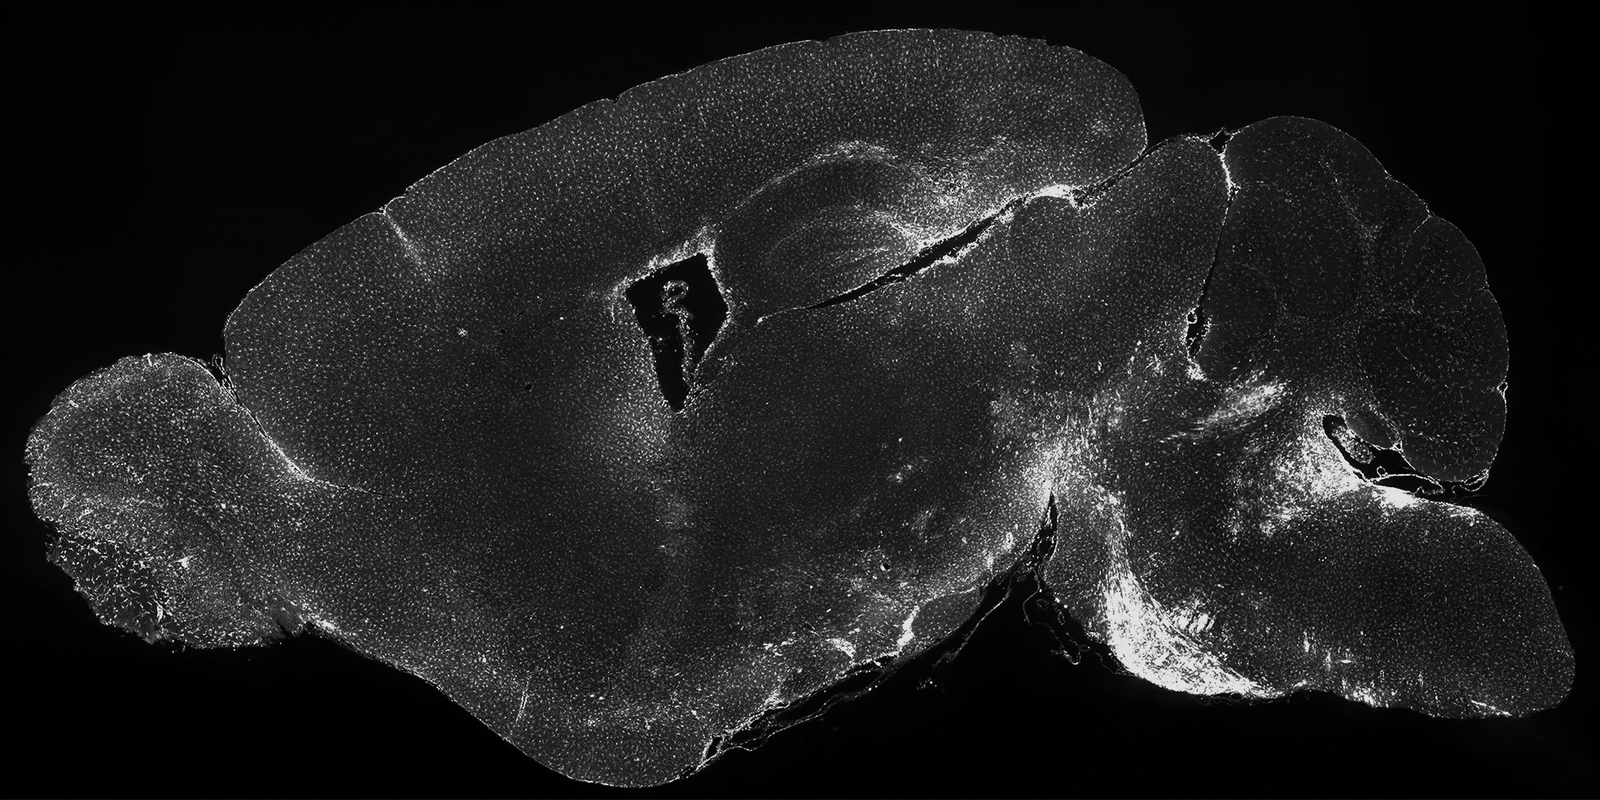

In the figure below, the Neuroinflammation Tissue Clearing Kit was used to measure the expression of Iba1 in response to either lipopolysaccharide (LPS) or murine coronavirus (MuCoV) treatments. The zoomed in regions demonstrate that the response to LPS is relatively homogeneous throughout the brain, whereas MuCov results in a very heterogeneous patterns with the Iba1 expression level differing dramatically across brain regions. This kit allows users to measure neuroinflammatory responses like those seen below.

In the figure below, coronavirus infected mouse brain displaying Increased levels of neuroinflammation in response to the infection. Bright swaths of Ibal expression can be seen in many regions including pons (box area).